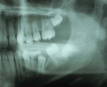

Molar migrations after loss of first molars, 8-year history: 1999

Figure 28

Molar migrations after loss of first molars, 8-year history: 2003

Figure 29

Molar migrations after loss of first molars, 8-year history: 2007

Figure 30

In 1998, a 7-year-old boy was brought in for emergency care with the chief complaint of toothache of the mandibular left permanent first molar. The malformed tooth was non-restorable and extracted, with no other treatment options. The child was not returned for continuing routine care but was returned on an emergency basis in 1999. He had a dentoalveolar abscess of the severely carious maxillary left permanent first molar, and the tooth was judged non-restorable (Figure 28). That molar was extracted. The patient was not returned to the office again until 4 years later, in 2003. The maxillary second molar had migrated into good position distal to the second premolar, and the third molar followed into place (Figure 29). The mandibular second molar was tipped mesially, followed by the crown of the third molar. Four years after that (2007), the patient returned as a 15-year-old. The second and third molars had migrated into position, with no orthodontic intervention (Figure 30).